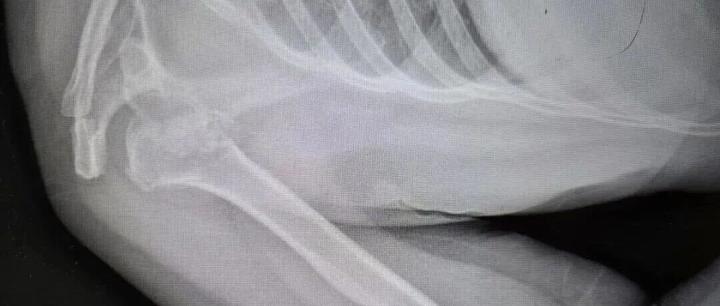

河南50岁女子睡梦中,肩膀骨头竟碎成七八块!医生:极为罕见